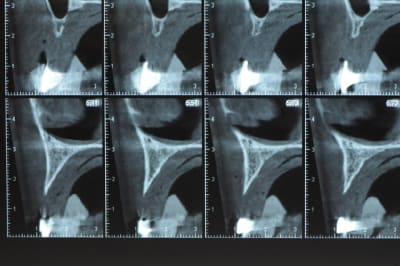

un cas pour PXAV.

ça c'est le domaine de pxav.

qu'en penses tu ?

j'ai besoin de 4 implants au maxillaire pour faire tenir son complet.

dans la zone postérieur, pas de problème, mais devant, c'est une autre histoire.

Non sans décorner, superbe cas de début pour expansion, bone splitting et tout et tout.

la corticale a l'air tiptop, par contre en cas d'expansion il faut eventuellemnt augmenter le nombre d'implant à 6 pour compenser eventuellement le manque d'epaisseur 'avis personnel)

Je suis sceptique sur la gestion de ce cas par bone splitting puisqu'il met parait très difficile d'obtenir un volume osseux peri-implantaire crestal suffisant et satisfaisant.

+1 Olive, ce serait à mon avis plus prédictible avec des greffes. Je doute qu'on puisse obtenir suffisamment d'os en vestibulaire et en palatin des implants en splittant une crête aussi fine.

De ce que j’ai vu du cas de D57 c’est me semble t il un magnifique cas d’expansion, ce qui ne veut pas dire rien d’autre

Ce n'est pas vraiment un consensus mais plutot du bon sens. Si tu as une crête en profil de lame de couteau cela signifie que tu as une fusion des corticales vestibulaire et palatine et donc absence de spongieux, ce qui comme tu le sais n'est pas indiqué en implanto (cj os de marbre par exemple)

Il me semble que Palti ou encore Szmukler-Moncler recommandent un minimum de 2-3mm. Si c'est plus fin, greffe d'apposition et GBR.

Dans ton cas il te faudrait abaisser la crête de 3 bons mm pour arriver à cette épaisseur.

Une petite étude de ton cas D57

Sous réserves bien sur de voir l’animal en vrai

Les zones exploitables radiologiquement parlant:

Coupes implant

2,3 40100

4,96 35130 avec sinus lift mais difficile

5,25 35150

6,02 35130

6,78 35115 après réduction de hauteur de crête

7,26 35115 après réduction de hauteur de crête

8,51 35150

10,43 40115 ou 50115

11,10 40115

Ce qui nous fait 9 implants possible évidement avec un comblement de sinus on augmenterait encore les zones implantable mais ce n’est pas le but recherché, avec 8 (4+4) il doit être possible de faire une belle barre support de complet